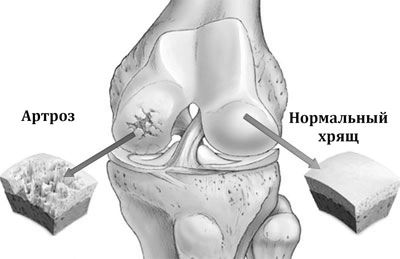

Чому погіршується стан при надлишкових навантаженнях на уражені суглоби, зрозуміти нескладно. В одній з книг Євдокименко порівнює хрящ з підшипниковий механізмом. Зруйнований артрозом суглоб перестає бути округлим, «підшипник» покривається мікротріщинами і заусенцами, а мастило стає густою і в'язкою.

Якщо запускати такий механізм, чи стане він від великих навантажень знову гладким? Або, навпаки, він швидше зруйнується? Відповідь очевидна. Саме тому від неправильних вправ з неточно розрахованими навантаженнями і невірної технікою виконання суглоб зруйнується швидше.